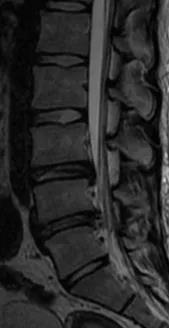

内镜下摘除突出髓核后的MRI表现